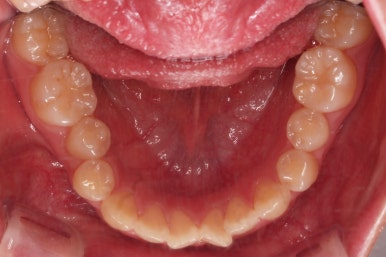

아래 치열이 우측으로 치우친 양상이었어요.

아래 중앙선이 윗니의 정중선에 비해 우측으로 많이 쏠려있고요.

전반적으로 아래 치열이 우측으로 가 있어서 특히 송곳니 부분에서의 반대교합이 두드러졌어요.

윗니는 가지런하게 하는 동안 아랫니는 중앙선을 개선하기 위해 미니스크류를 이용해 뒤로, 뒤로 계속 당겨주게 됩니다.

힘 조절도 적절히 해가면서 아래 치열을 뒤로뒤로 옆으로 옆으로 밀어줍니다.

만족스러운 수준까지 정중선을 개선하고 교합도 개선한 뒤, 마무리를 해줍니다.

가지런한 느낌, 교합, 중앙선, 반대교합 등 모든 면에서 개선이 되었고요.